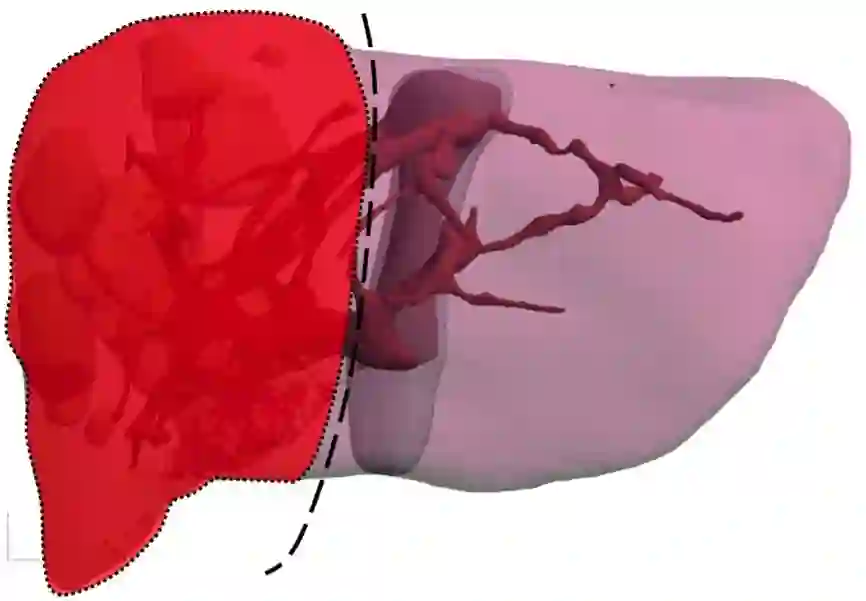

iii. 治疗经过:2017-04-20 行扩大右半肝切除术+胆囊切除术

1. 该患者诊断为结肠癌伴多发性肝转移,肝脏MR增强示肝右叶及左内叶可见多发团状异常信号影,考虑为转移瘤。较大者位于V及VI段,大小约13*7cm,肿瘤病灶大,负担重,转移瘤肝转移灶初始不可切除

3. FOLFIRI+西妥昔单抗(爱必妥)方案治疗8周期后,患者身体状况良好,无基础性疾病,治疗愿望强烈且肝转移灶可切除。采用了分期切除,肝转移灶优先切除的理念进行手术治疗,围手术期无并发症发生